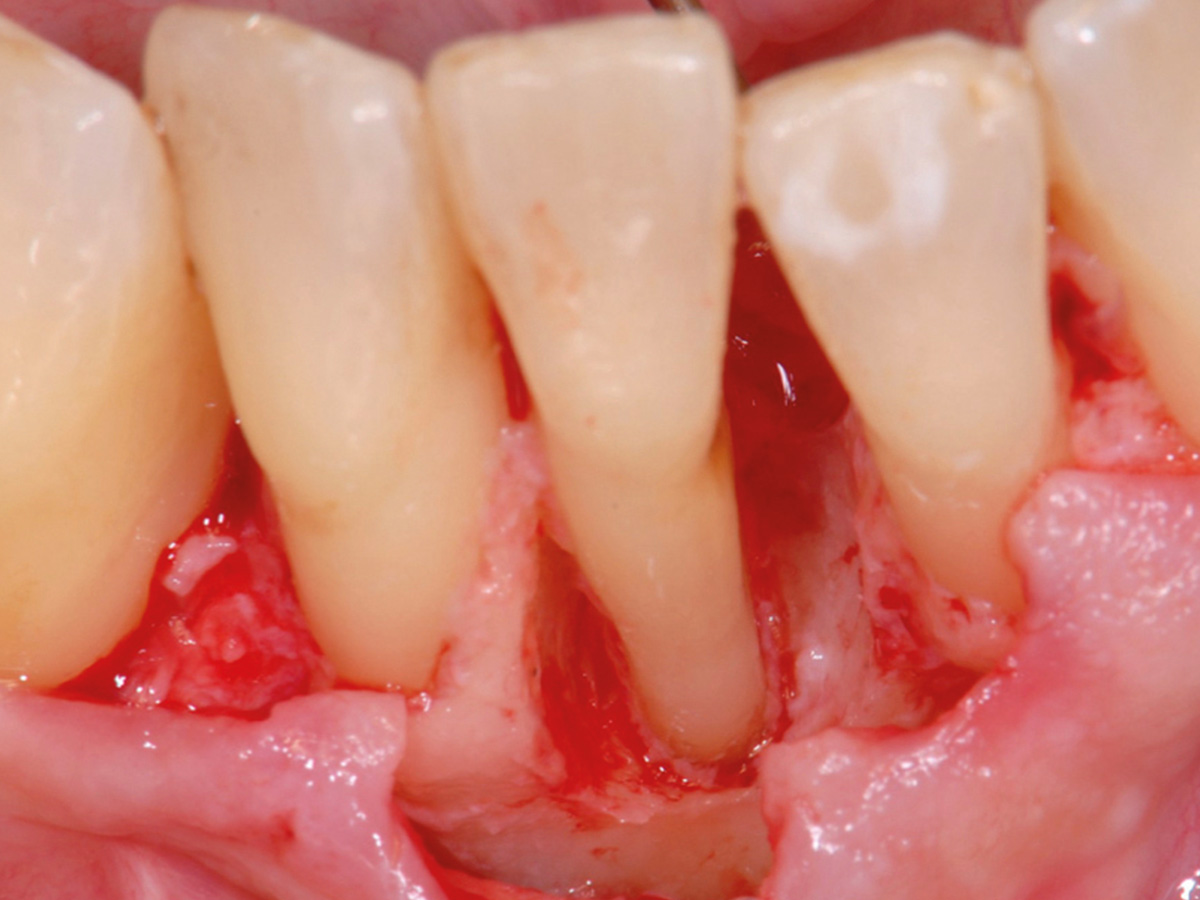

Nach der nicht-chirurgischen Parodontitis-Therapie verbleiben an stark parodontal-kompromittierten Zähnen häufig noch Resttaschen, die im Rahmen einer erfolgreichen Parodontitis-Therapie weiter behandelt werden müssen. Zu diesem Zeitpunkt stellt sich also die Frage, ob der einzelne Zahn mittels parodontalchirurgischer Verfahren erhaltungsfähig ist oder doch besser extrahiert werden sollte. Regenerative parodontalchirurgische Verfahren spielen an dieser Stelle eine große Rolle.Doch wann sollte welche chirurgische Technik, wann sollten welche regenerativen Materialien verwendet werden? Der Workshop vermittelt Kenntnisse, wann ein Zahnerhalt mittels Regeneration parodontaler Defekte erfolgreich möglich ist und wann welche chirurgischen Techniken und regenerativen Materialen zielführend sind.

Die Teilnehmer trainieren am Tiermodell verschiedene mikrochirurgische Techniken der Parodontalchirurgie. Zusätzlich werden die Schritte regenerativer Maßnahmen an unterschiedlichen Defekten (z.B. an 1-, 2- und 3-wandigenDefekten) mit den verschiedenen regenerativen Materialien geübt.